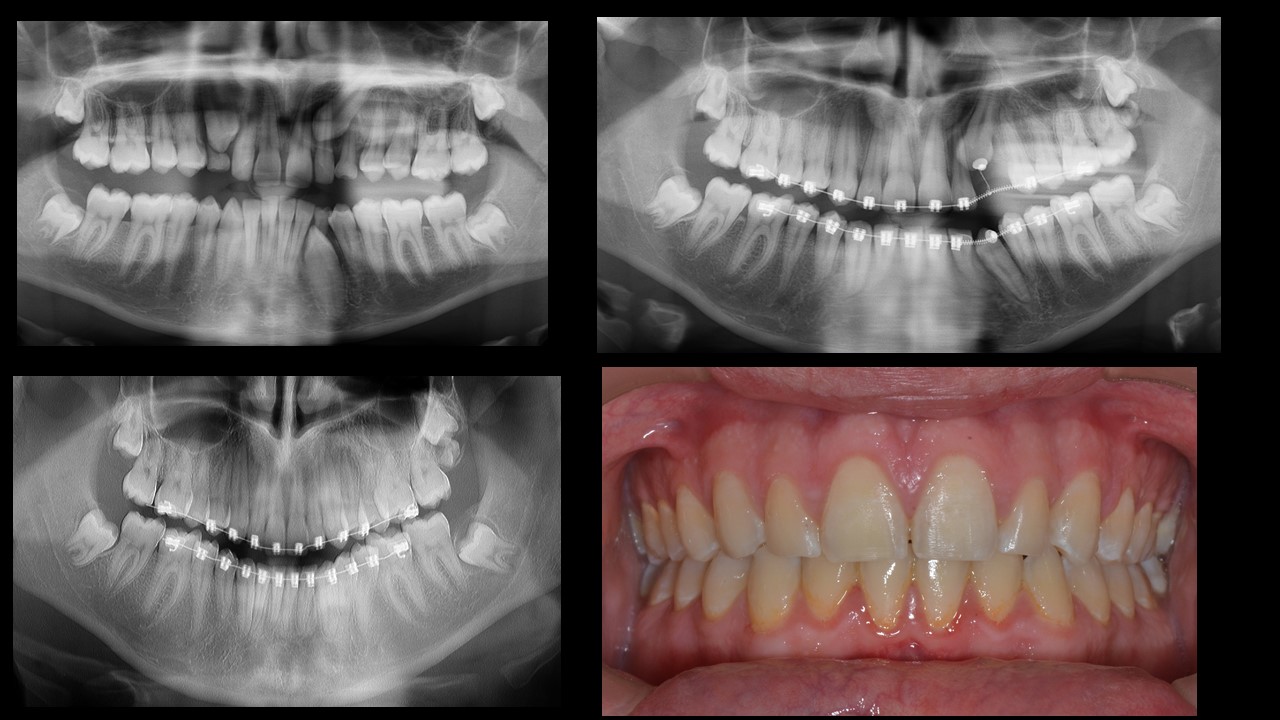

Impacted canines present a big challenge for the clinician and special attention should be given to early extraction of primary teeth (which block the cuspid) and then pull the tooth in the correct direction while space is opened even beyond need.